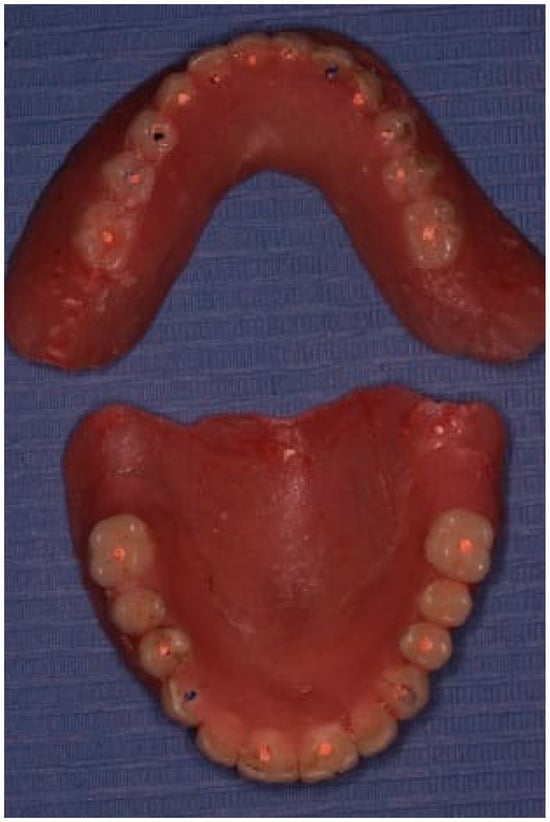

The edentulous spaces in the lower partial denture were then restored to replace the extracted teeth. The existing upper denture was positioned with the lower denture to re-evaluate the vertical dimension, aesthetics, and phonetics (Figure 3).

The dentures were utilized to develop a prosthetically guided implant placement protocol. Each tooth of the dentures was perforated from the occlusal aspect to facilitate the insertion of a gutta–percha cone at the center of each tooth (Figure 4).

Figure 3. Image showing the upper and lower dentures.